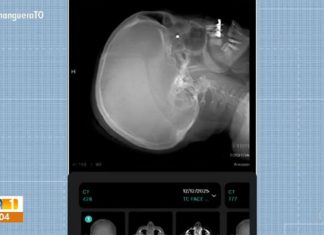

Mulher atingida por tiro em barraca de parque está com chumbinho alojado no olho

Mulher é atingida por chumbinho de barraca de tiro durante festa de Natal em Palmas

A servidora pública Isabel Cristina Rocha, que foi atingida no olho por um chumbinho enquanto...